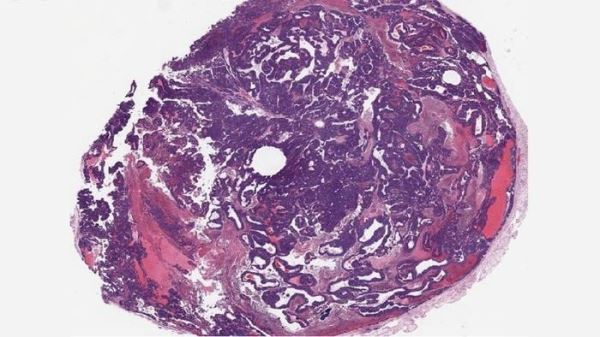

[Фото: dos Santos lab/CSHL]